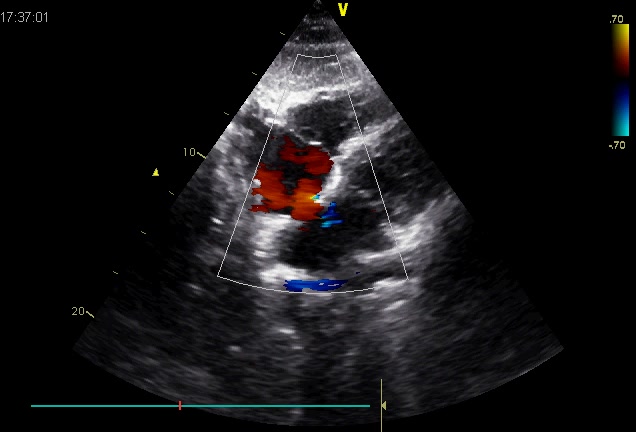

二尖瓣短轴观并反流